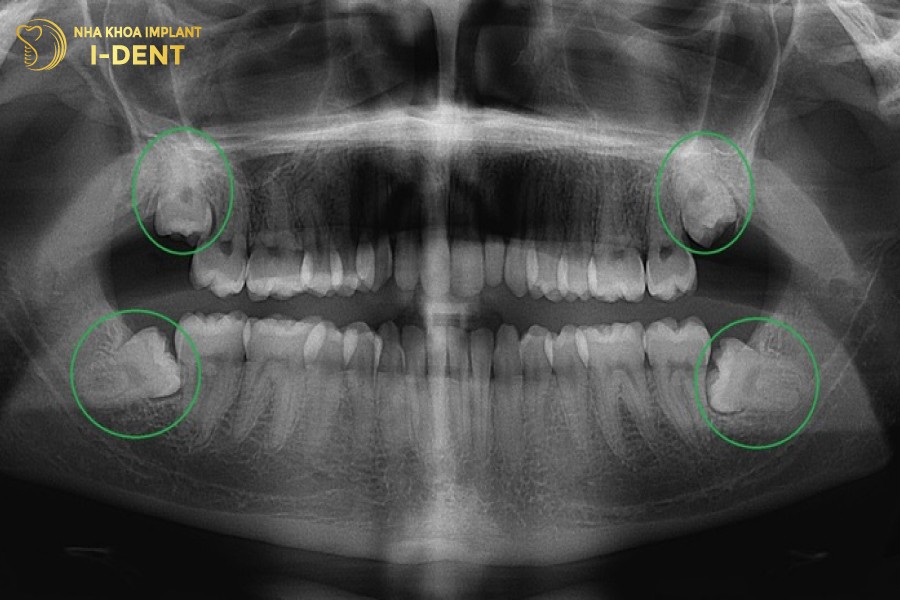

Răng khôn (răng số 8) mọc ở vị trí cuối cùng trên cung hàm, kế bên răng hàm lớn số 7. Răng khôn có thời gian mọc muộn nhất so với những răng khác, thường là vào độ tuổi trưởng thành từ 17-25 tuổi, khi đã trải qua giai đoạn thay răng và cấu trúc xương hàm đã phát triển ổn định.

Theo lý thuyết, một người trưởng thành sẽ mọc 4 chiếc răng khôn ở vị trí 4 góc hàm, tuy nhiên tùy vào cơ đia và cấu trúc hàm của mỗi người mà sẽ có số lượng răng khôn mọc khác nhau. Có người mọc đủ cả 4 răng khôn, có người lại không mọc cái nào, thông thường một người sẽ chỉ mọc từ 1 đến 3 chiếc răng khôn.